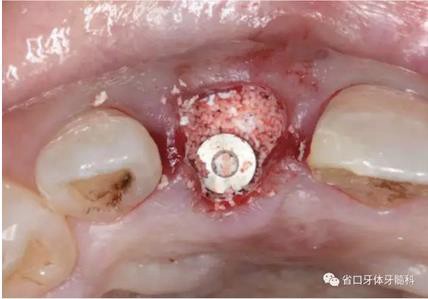

圖16 跳躍間隙植骨

圖17 跳躍間隙植骨

本病例患牙冠根折而不能保留,考慮到患牙具有完整的唇側(cè)骨板,且 其厚度約1mm,中厚型生物型,局部無急性炎癥,牙槽窩靠近根尖及腭側(cè) 區(qū)能提供足夠的骨量,基本符合即刻種植的適應(yīng)證。通過微創(chuàng)拔牙得以保 存拔牙窩的軟硬組織完整。種植體的正確三維位置是即刻種植成功的重要因 素。種植位點(diǎn)應(yīng)該位于缺牙間隙的近遠(yuǎn)中中點(diǎn),種植體近遠(yuǎn)中面要距離鄰牙 >1.5mm,且整體靠腭側(cè)植入,以使得種植體唇側(cè)面位于牙弓外形連線內(nèi)側(cè) >2mm,并保留唇側(cè)骨板內(nèi)側(cè)面與種植體唇側(cè)面之間約2mm的跳躍間隙。 在冠根向上,種植體平臺(tái)應(yīng)該位于未來修復(fù)體唇側(cè)齦緣中點(diǎn)下3mm。鑒于 唇側(cè)骨板主要由束狀骨組成,在牙齒拔除后基本上趨于吸收,從而造成種植 體唇側(cè)骨質(zhì)不穩(wěn)定而影響美觀風(fēng)險(xiǎn)。因此,通過跳躍間隙植骨,以低替代率骨移植材料充填并促進(jìn)間隙骨生成,最終獲得種植體周的穩(wěn)定骨質(zhì),為軟組 織的穩(wěn)定提供支撐。